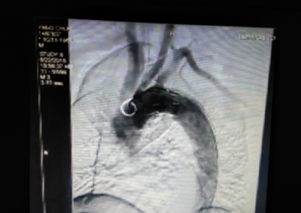

我院成功开展市属医院首例先心病介入封堵术 不用开刀,不会在体表留下疤痕,只需进行局部皮肤麻醉,通过穿刺右侧股静脉插入一根几毫米的导管,将封堵器送至缺损部位释放,先天性心脏病就得到了根治。不久前,15岁的小章在我院成功接受了先天性心脏病介入封堵术,他的心脏结构和功能恢复了正常,学习和生活也得到了恢复。...